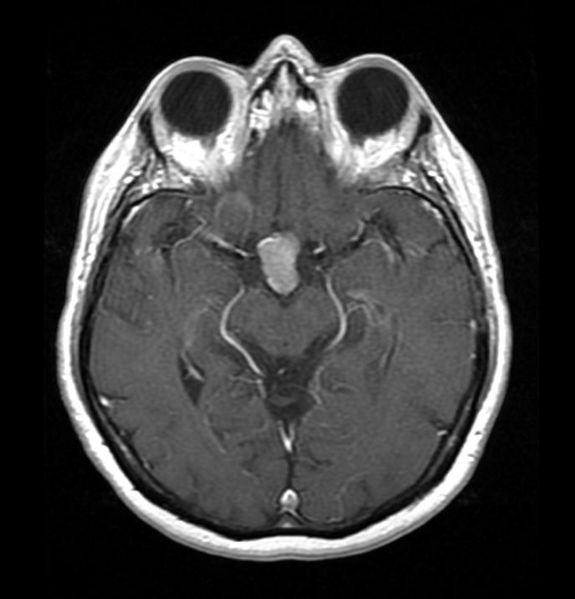

KC is currently undergoing Radiation Therapy three times a week to shrink her growing brain tumors. In April 2025, we found out that the tumor on Kc’s pituitary gland had grown from 2.3 cm to 10.5 cm. Due to her tumor being larger than 2.0 cm, Kc is ineligible to receive a Transnasal Transsphenoidal Surgery (less invasive surgery that removes brain tumors via the nose versus removal directly through the cranium). Kc silently continues to struggle mentally, physically, and financially, always placing others and their needs and wants above her own. Medication management and Radiation Therapy to shrink her tumors were recommended as the best modality of treatment. Unfortunately, Kc is not responding to treatment as doctors had hoped. Kc will need to undergo brain surgery once Radiation Treatment ends (last Radiation Treatment date: September 5, 2025) to remove the tumors from her brain.